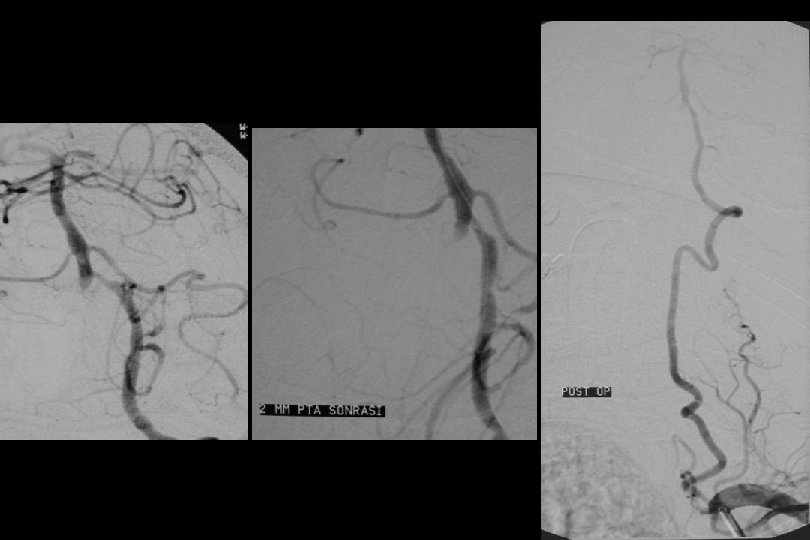

52 y kadın efektiv/test edilmiş ikili antiagregan ted altında iken multipl TIA Basit PTA sonrası

1. Yıl kontrol

1 yıl kontrol PTA Sonrası